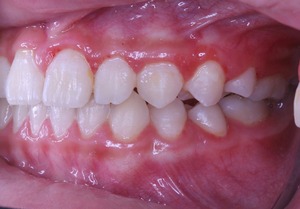

横から生えてきた永久歯も向きは悪いですが、かなり良い方向に降りてきました。

一方で出てきたときの状況は